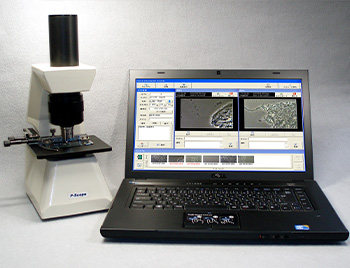

位相差顕微鏡は、そんな物体が光の波長に与える位相のずれを明暗の差として捕らえ、くっきりとした輪郭を観察できるのが特徴の機器です。

これにより、今まで観察が難しかった、「微生物を生きたまま観察する」事が可能になるのです。

殺菌水の効果確認、除菌・殺菌治療法(パーフェクトペリオ、3-Mix法、レーザー、オゾンなど)の効果確認、口腔内細菌の観察と差別化など、主に歯科医院などでご利用・観察いただいております。

また動物病院などでは、コクシジウムやジアルジアの観察などにも役立っています。